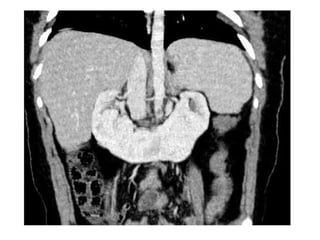

2-Pacake / Discoid Kidney :

-Bilateral fused pelvic kidneys , usually near

the aortic bifurcation

Pancake kidney with APKD

2-Pacake / DiscoidKidney : -Bilateral fused pelvic kidneys , usually near the aortic bifurcation